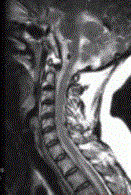

- 多项选择题3.关于MRI的描述正确的是(提示患者行脊柱MRI平扫及增强检查,显示如下图)

A、颈髓增粗,其内可见片状高信号影

B、胸髓可见多发片状高信号影

C、脊髓未见异常

D、MRI增强检查可见片状强化

E、脊髓空洞

F、脊髓肿胀